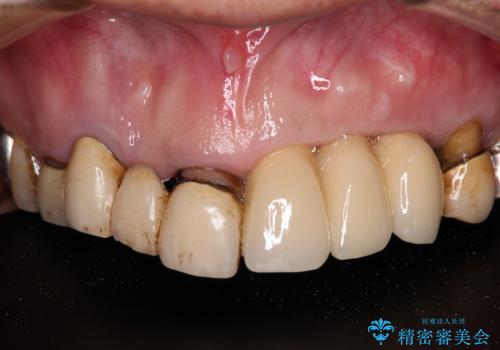

治療により前歯は非常に安定しましたが、インプラント部の両隣、特に反対側の前歯はクラウンのやり直しが必要な状態であったので、今後反対側の治療も実施していく予定です。